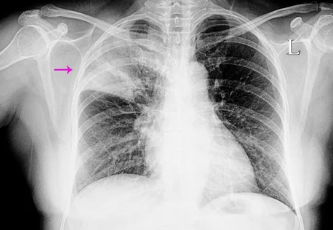

4. 폐렴, 어떻게 진단하나요? 병력 청취부터 영상 검사까지

폐렴 진단은 환자의 병력 청취, 신체 검사, 혈액 검사, 가래 검사, 흉부 X-ray, CT 등 다양한 검사를 통해 이루어집니다.

폐렴 진단 검사:

- 흉부 X-ray: 폐렴 병변 위치와 크기를 확인합니다.

- CT: 흉부 X-ray보다 더 정밀하게 폐렴 병변을 확인할 수 있습니다.